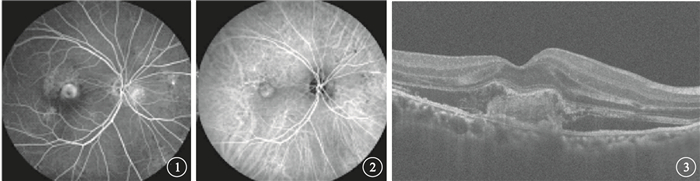

前瞻性、無對照、開放性研究。2014年4~8月在武漢大學人民醫院眼科經熒光素眼底血管造影(FFA)和吲哚青綠血管造影(ICGA)檢查確診為滲出型AMD的20例患者20只眼納入本研究。其中,男性19例19只眼,女性1例1只眼。年齡52~79歲,平均年齡(66.65±8.94)歲。所有患眼均行最佳矯正視力(BCVA)、眼壓、眼底彩色照相、FFA、ICGA和光相干斷層掃描(OCT)檢查。BCVA檢查采用糖尿病視網膜病變早期治療研究視力表進行;眼壓測量采用日本Topcon公司非接觸眼壓計進行;眼底彩色照相采用日本KOWA nonmydα-D免散瞳眼底照相機進行;FFA檢查采用德國海德堡共焦激光眼底造影儀進行;OCT檢查采用蔡司Cirrus HD-OCT進行,由同一位醫師采用512×128模式及高清掃描模式測量中心視網膜厚度(CRT),存在偏差者行人為校準。患眼BCVA為8~80個字母,平均BCVA為(41.20±22.61)個字母。FFA、ICGA檢查發現,所有患眼黃斑區CNV病灶滲漏明顯(圖 1,2)。OCT檢查發現,所有患眼黃斑區視網膜水腫,伴神經上皮脫離(圖 3)8只眼,伴視網膜色素上皮(RPE)脫離3只眼;CRT為152~770μm,平均CRT為(345.25±131.96)μm。所有患眼均符合滲出型AMD的臨床診斷標準[8-11]。

前瞻性、無對照、開放性研究。2014年4~8月在武漢大學人民醫院眼科經熒光素眼底血管造影(FFA)和吲哚青綠血管造影(ICGA)檢查確診為滲出型AMD的20例患者20只眼納入本研究。其中,男性19例19只眼,女性1例1只眼。年齡52~79歲,平均年齡(66.65±8.94)歲。所有患眼均行最佳矯正視力(BCVA)、眼壓、眼底彩色照相、FFA、ICGA和光相干斷層掃描(OCT)檢查。BCVA檢查采用糖尿病視網膜病變早期治療研究視力表進行;眼壓測量采用日本Topcon公司非接觸眼壓計進行;眼底彩色照相采用日本KOWA nonmydα-D免散瞳眼底照相機進行;FFA檢查采用德國海德堡共焦激光眼底造影儀進行;OCT檢查采用蔡司Cirrus HD-OCT進行,由同一位醫師采用512×128模式及高清掃描模式測量中心視網膜厚度(CRT),存在偏差者行人為校準。患眼BCVA為8~80個字母,平均BCVA為(41.20±22.61)個字母。FFA、ICGA檢查發現,所有患眼黃斑區CNV病灶滲漏明顯(圖 1,2)。OCT檢查發現,所有患眼黃斑區視網膜水腫,伴神經上皮脫離(圖 3)8只眼,伴視網膜色素上皮(RPE)脫離3只眼;CRT為152~770μm,平均CRT為(345.25±131.96)μm。所有患眼均符合滲出型AMD的臨床診斷標準[8-11]。